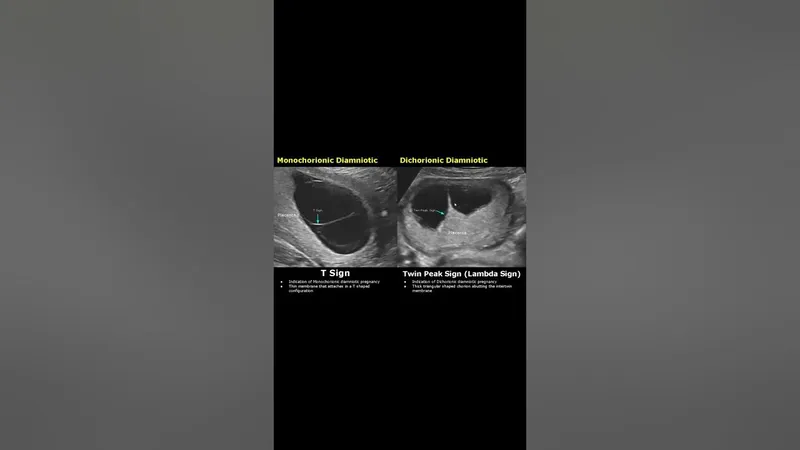

- T-sign: MCDA (thin membrane)

- Lambda (λ) sign / Twin peak sign: DCDA (thick membrane)

⭐ Chorionicity (determined by ultrasound via T-sign/Lambda sign) is the single most important prognostic factor in twin pregnancies.

- Ultrasound: Lambda (λ) sign indicates dichorionicity; T-sign indicates monochorionicity.